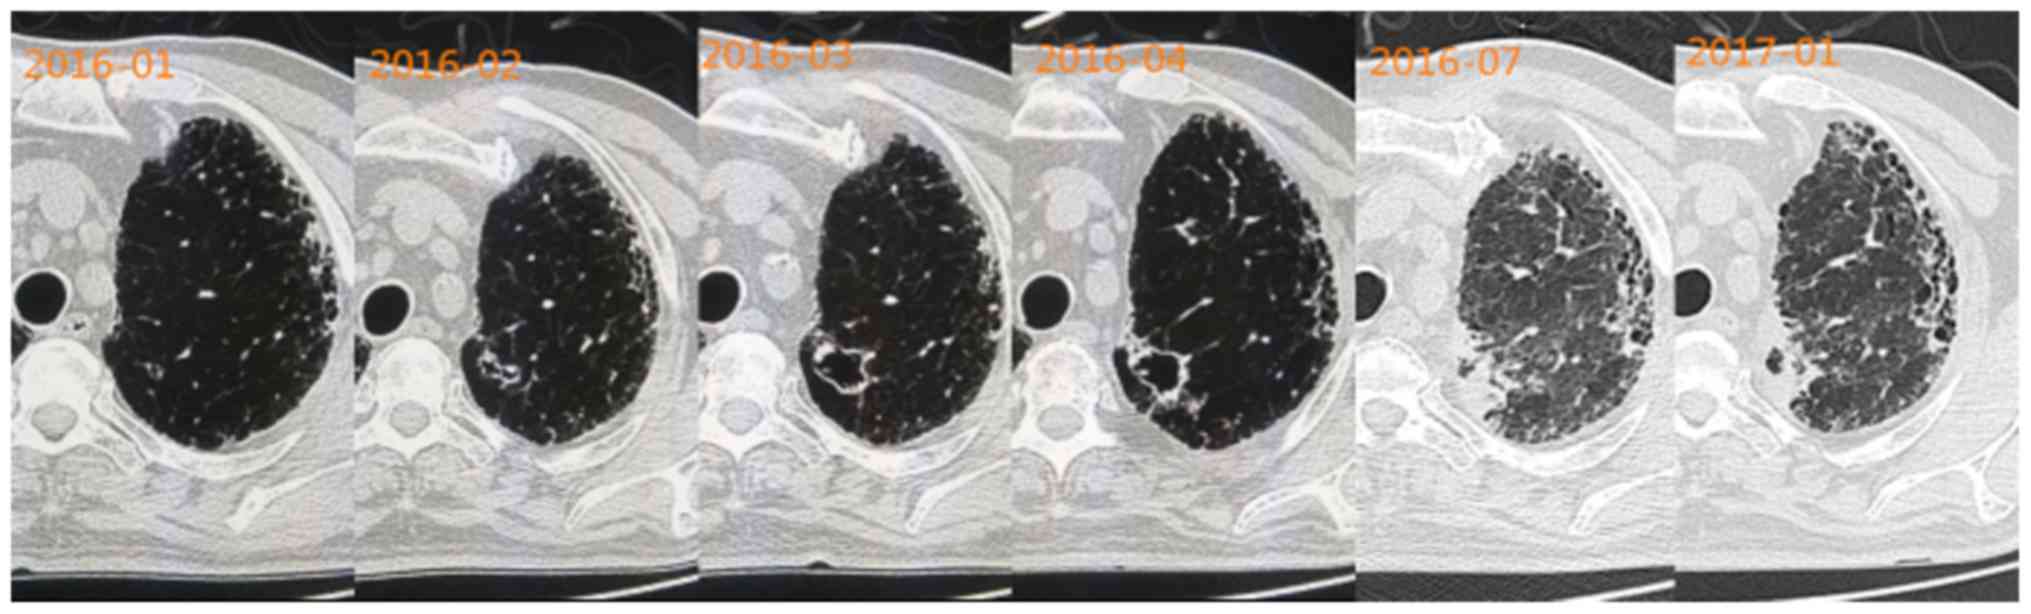

One 60-year-old patient who had interstitial lung disease presented with a small cystic lesion on CT images in January 2016. A chest CT performed after a month revealed that the cystic lesion had become larger, and its wall had become slightly irregularly thickened, compared with the previous CT findings. Close clinical follow-up on a monthly basis was recommended for the patient. Over the following two months, the cystic lesion grew larger than previously and seemed to be uniform in size, but its wall became irregularly thickened with certain malignant observations, including irregular margin, small spicules, signs of pleural indentation, ground-glass opacity and clear nodules. This cystic lesion was suspected to be a malignant lesion. Finally, imaging examinations revealed that the cystic lesion was getting smaller and the wall was getting thicker (Fig. 4).